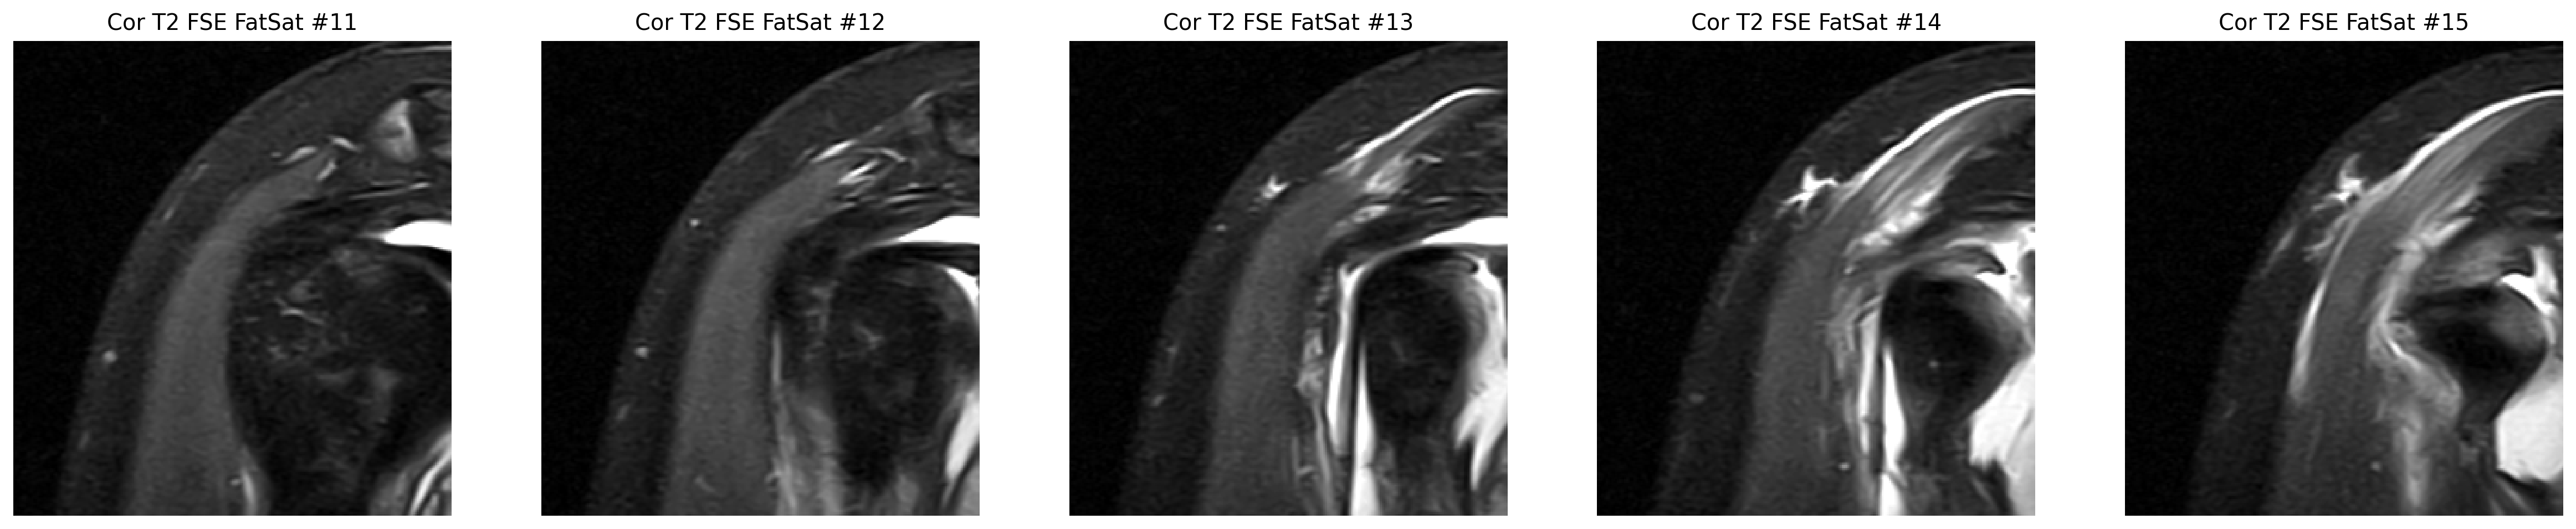

The strongest image-only read is a smaller tear or split on the joint-facing side of the supraspinatus tendon where it attaches to bone.

The cuff finding was checked in coronal and sagittal views, while the labrum was reviewed on axial arthrogram slices.